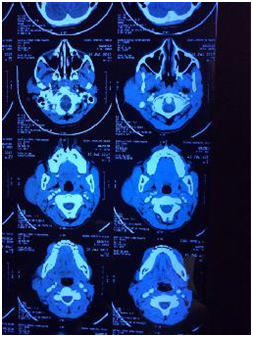

Ultrasonography showed heterogenous parenchyma with multiple hypoechoeic lesions in the left parotid. Computed tomography complemented the findings of sonography. Fine needle aspiration of parotid showed polymorphic population of lymphoid cells and plasma cells. Peripheral blood gave a picture of normal eosinophil count (2%). With a provisional diagnosis of pleomorphic adenoma, superficial parotidectomy was carried out. Post operative recovery was good with no complications.

Patient has been following up since six months with no evidence of recurrence or complications (Figure 1-3).

Figure 1 CT scan of Face axial cut showing left parotid swelling.